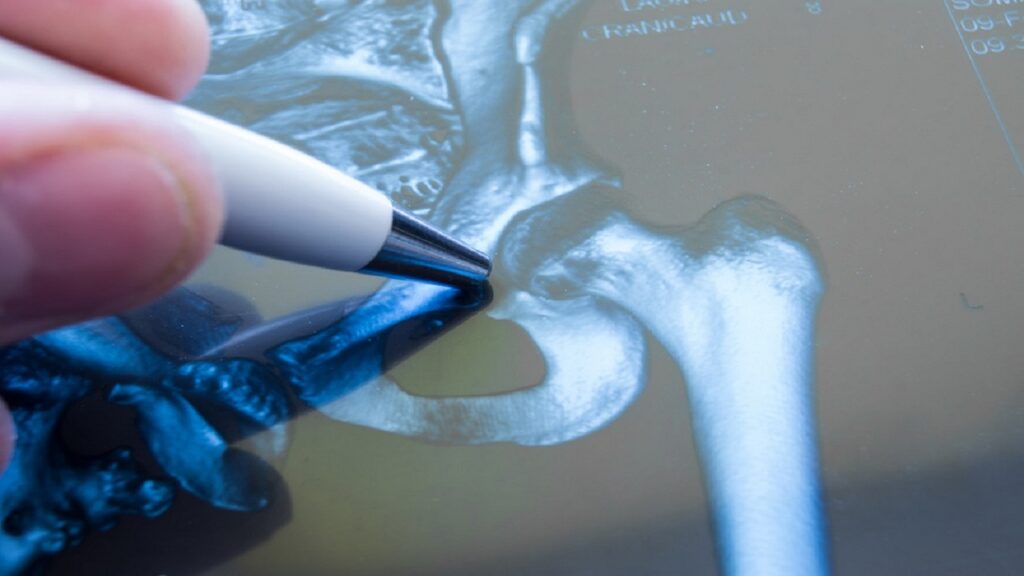

Most hip fractures develop in the upper thigh, or femur bone, and necessitate surgery. Sometimes, patients attempt to endure the pain rather than seek urgent medical care – even if they are unable to bear weight. Delays in treatment might result insignificant, even dangerous, consequences. Every patient who has suffered a hip fracture as a result of a fall should have it repaired within 24-48 hours.

Any individuals 60 and older with ground-level fall fractures are immediately treated in our orthopedic department at ONP Hospital. Based on the area of the fracture, our orthopedic surgeons can replace the entire hip, a portion of the hip, or put a permanent rod inside the bone. While recovery is not without pain, the degree of pain and difficulties is significantly reduced following rapid treatment.